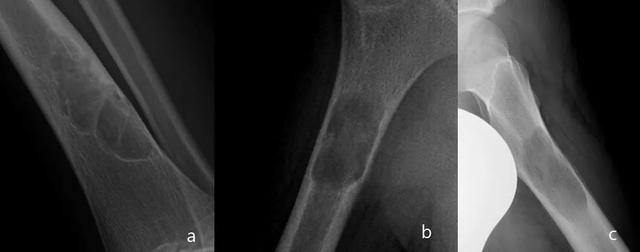

图1.透明/裂解性骨病变边缘的Lodwick分类:类型1:包括1A:薄的,硬化边缘(a); 1B:边界清晰,但不硬化(b); 1C:模糊边界(c); :虫噬样(d); 侵蚀性(e)。

图2.局部病变。IA型:硬化的明确边际(a)。IB型:明确界限,非硬化(b)。类型IC:边界不明确(c)。

图3.虫噬样(a)。侵蚀性(b)。